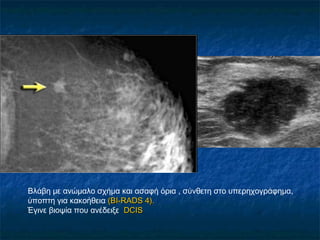

Βλάβη με ανώμαλο σχήμα και ασαφή όρια , σύνθετη στο υπερηχογράφημα,

ύποπτη για κακοήθεια ((BI-RADS 4).BI-RADS 4).

Έγινε βιοψία που ανέδειξε DCISDCIS